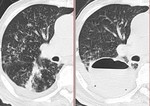

[Weekly Chest Cases]肺カルチノイド、CT所見について 2011-04-19